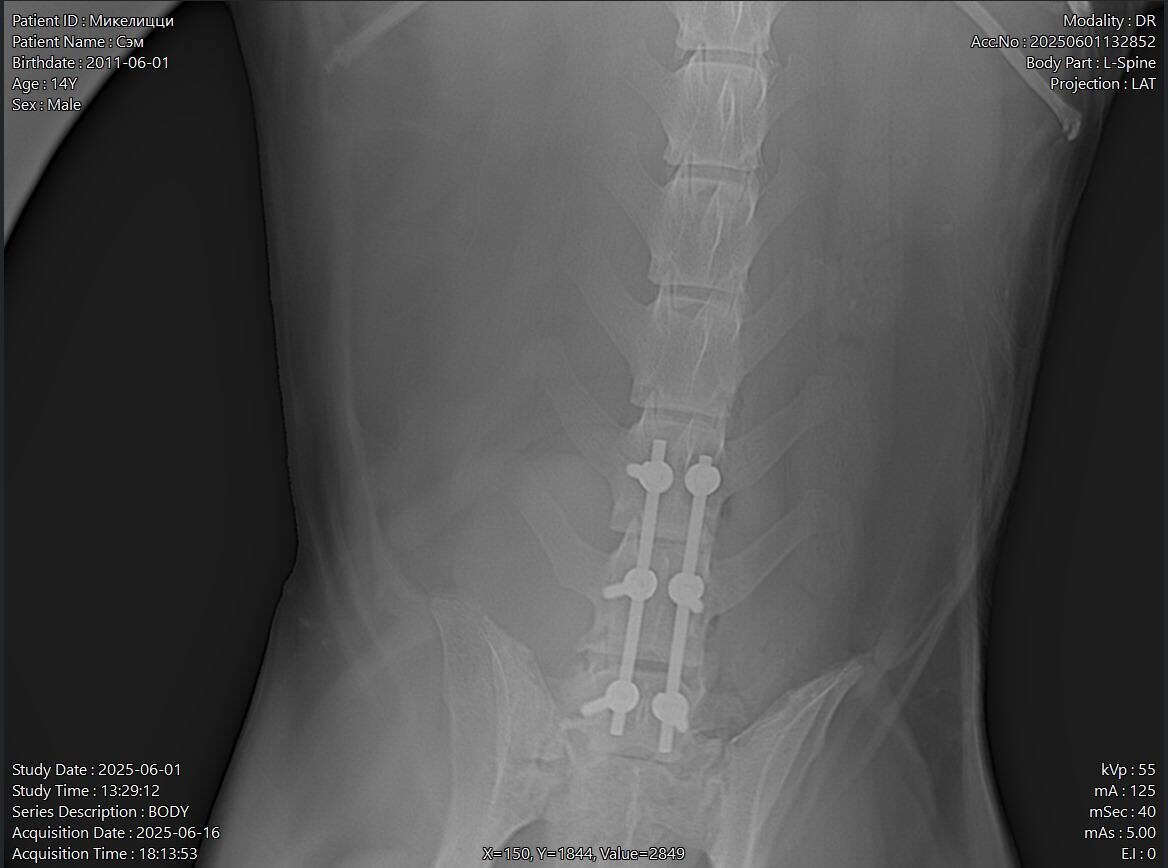

Sam was worse off than they expected. He woke last night after 6 hours of surgery. He couldn’t stand on his own today. He might come home tomorrow or Thursday.

Sam was worse off than they expected. He woke last night after 6 hours of surgery.

He couldn’t stand on his own today. He might come home tomorrow or Thursday.